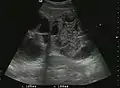

They can be single or multiple, with variable size, generally less than 20 mm (congenital). Rarely, sizes can reach several centimeters, leading up to the substitution of a whole liver lobe (acquired, parasitic). They may be associated with renal cysts; in this case the disease has a hereditary, autosomal dominant transmission (von Hippel Lindau disease).

The ultrasound appearance is a well defined lesion, with very thin, almost unapparent walls, without circulatory signal at Doppler or CEUS investigation. The content is transonic suggesting fluid composition. The presence of membranes, abundant sediment or cysts inside is suggestive for parasitic, hydatid nature. Posterior from the lesion the acoustic enhancement phenomenon is seen, which strengthens the suspicion of fluid mass. They typically displace normal liver vessels but no vascular or biliary invasion occurs.

Hydatid liver cyst. Diagnostic criteria are the presence of membranes and sediment inside.